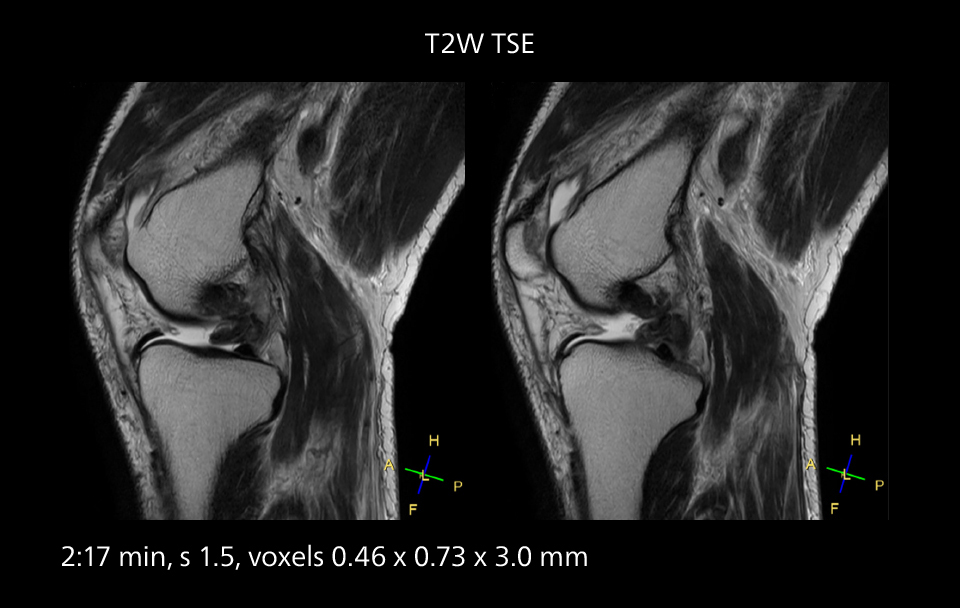

Crisp images are obtained with high resolution and short scan times using Elition X. A cyst can be seen.

Sannodai Hospital radiologists had been very satisfied with their Ingenia 3.0T with Compressed SENSE, however after acquiring SmartPath to Elition X they have demonstrated improved image quality and even higher speeds in imaging studies throughout the body, according to Dr. Makuuchi. “Generally, we were impressed by seeing that images are very sharp and have higher SNR than we used to get with our Ingenia 3.0T system,” he notes. “We were delighted to see that high image quality can be obtained in a short time thanks to the Elition with its powerful An example of increased imaging speed is in knee studies. “There is a definite scan time reduction for T2* mFFE and proton density TSE – both of these sequences benefit from much shorter repetition times,” he reports.

Overall, imaging time per sequence has been reduced since the Elition X upgrade. This can help reduce the risk of patient movement and the need for rescans. “As our hospital has many elderly patients, we consider it important to obtain high-quality data in a short time,” Dr. Makuuchi says. “Shorter imaging times are also useful for accepting emergency patients, because faster emergency studies have a reduced impact on the daily examinations schedule. In emergency cases it is also important that high quality images are obtained in a short time.”